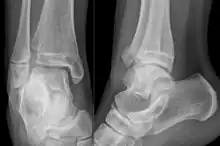

Sur les radiographies, on peut voir une fracture de la malléole médiale, de la malléole latérale et/ou du bord antéro-postérieur du tibia distal. Le bord postérieur (appelé malléole postérieure) est beaucoup plus fréquemment lésé que la face antérieure du tibia distal. Si les malléoles latérale et médiale sont brisées, on parle de fracture bimalléolaire (certaines d'entre elles sont appelées fractures de Pott (en)). Si la malléole postérieure est également fracturée, on parle de fracture trimalléolaire.[réf. nécessaire]

Vue AP en contrainte manuelle montrant une déchirure du ligament deltoïde.

Une fracture triplane de la cheville vue sur une radiographie standard